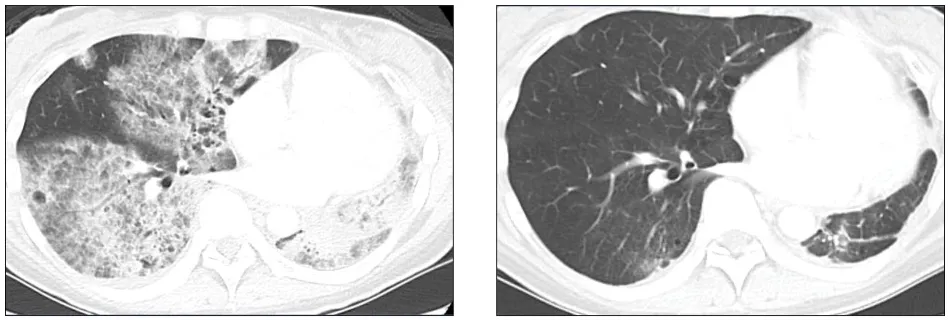

而影像学的变化,更让人震惊——在接受治疗约一年后(截至2025年4月报道),她体内的肿瘤缩小了87%,并且仍在持续缩小。从影像上看,原本大片模糊的病灶,如今明显“退场”。

治疗前后肺部影像对比:左为治疗前,右为治疗后

(来源:MSK官网)